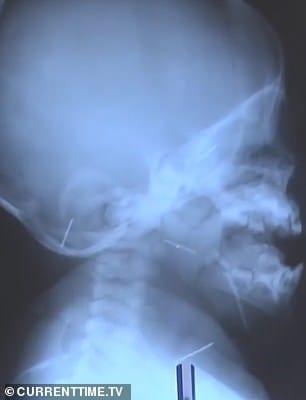

Ο μικρούλης νοσηλεύτηκε το προηγούμενο καλοκαίρι όταν ένας συγγενής ανακάλυψε μια βελόνα μέσα στο στόμα του. Το εννιά μηνών υπεβλήθη σε ακτίνες και εντοπίστηκαν 10 βελόνες.

Οι γιατροί προχώρησαν σε αρκετές επεμβάσεις προκειμένου να αφαιρέσουν τα μεταλλικά αντικείμενα από το βρέφος, που έφερε βελόνες σε κρανίο, μύτη, λαιμό, στήθος και πόδια. Όπως ανέφερε νοσοκομειακή πηγή, κάποιες από τις βελόνες είχαν σκουριάσει μέσα στο κορμάκι του όπου βρίσκονταν για περισσότερους από 3 μήνες. Αμέσως μετά το περιστατικό η μητέρα τέθηκε υπό κράτηση και παραδέχθηκε τις πράξεις της αποκαλύπτοντας και τον λόγο.